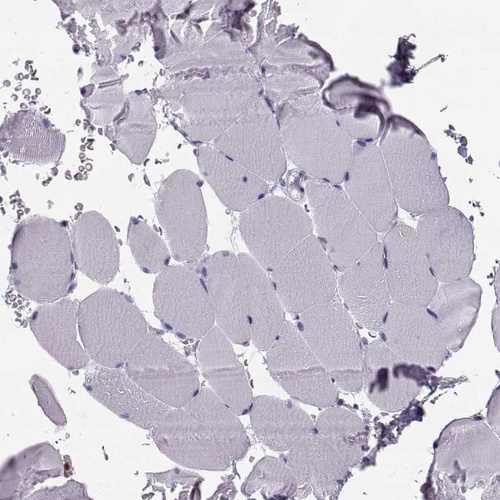

Immunohistochemical staining of human eye shows strong cytoplasmic positivity in the lens.